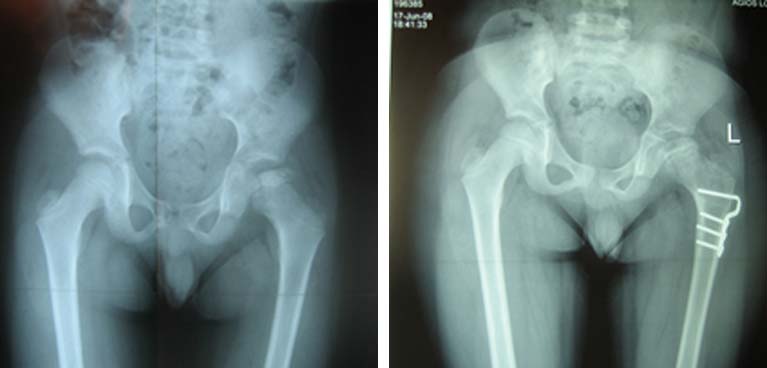

Οστεοχονδρίτιδα μηριαίας κεφαλής - Νόσος Parthes

Εικόνα ακτινολογική απεικόνιση αρχόμενης οστεοχονδρίτιδος ισχίου αριστερά, με ελάττωση ύψους της επίφυσης και γραμμή υποχονδρίου κατάγματος